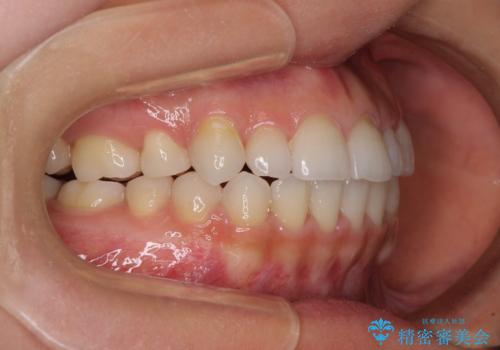

- 前歯のデコボコや八重歯、舌癖による開咬を気にして来院された患者様です。

目立たない装置を希望されたので、上顎が裏側装置のハーフリンガルを選択し、上顎小臼歯1本を抜歯して、補助装置を併用して矯正治療を行うこととしました。

補助装置を事前に使用したことで、あっという間に八重歯が改善し、ハーフリンガルにしては1年半もかからずに治療を終えることができました。